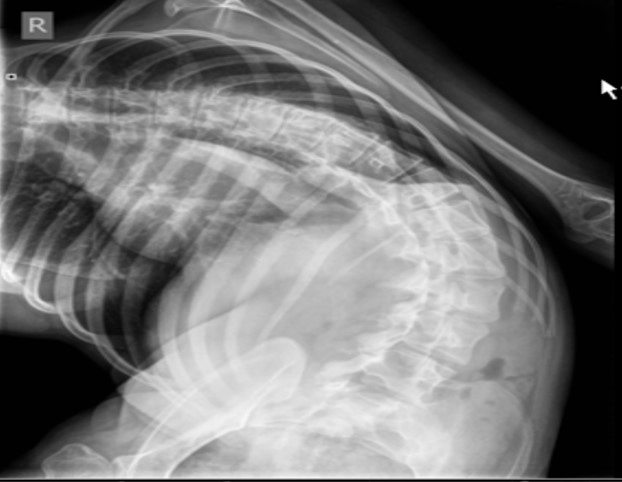

Физическое состояние пациента

Обеспечение проходимости дыхательных путей – недостаточное разгибание шеи

Возможные пути решения проблемы:

- Использование эндоскопической техники при интубации

- Тщательная оценка анатомии дыхательных путей перед операцией

- Прогнозирование трудной интубации с использованием шкалы Маллампати.